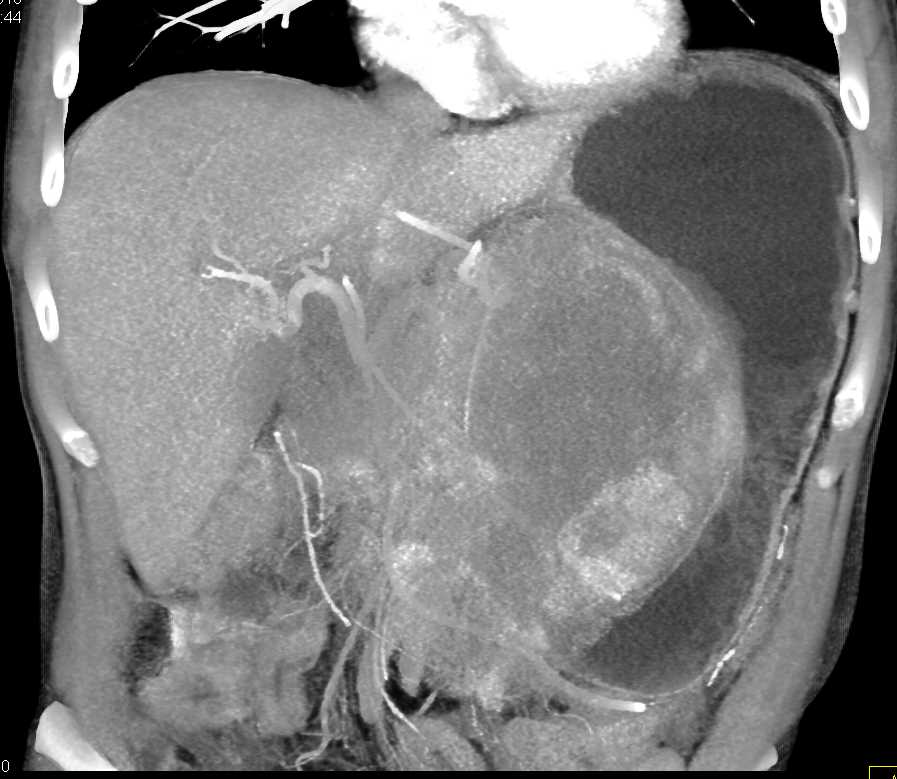

Lagre Gastric GIST Tumor